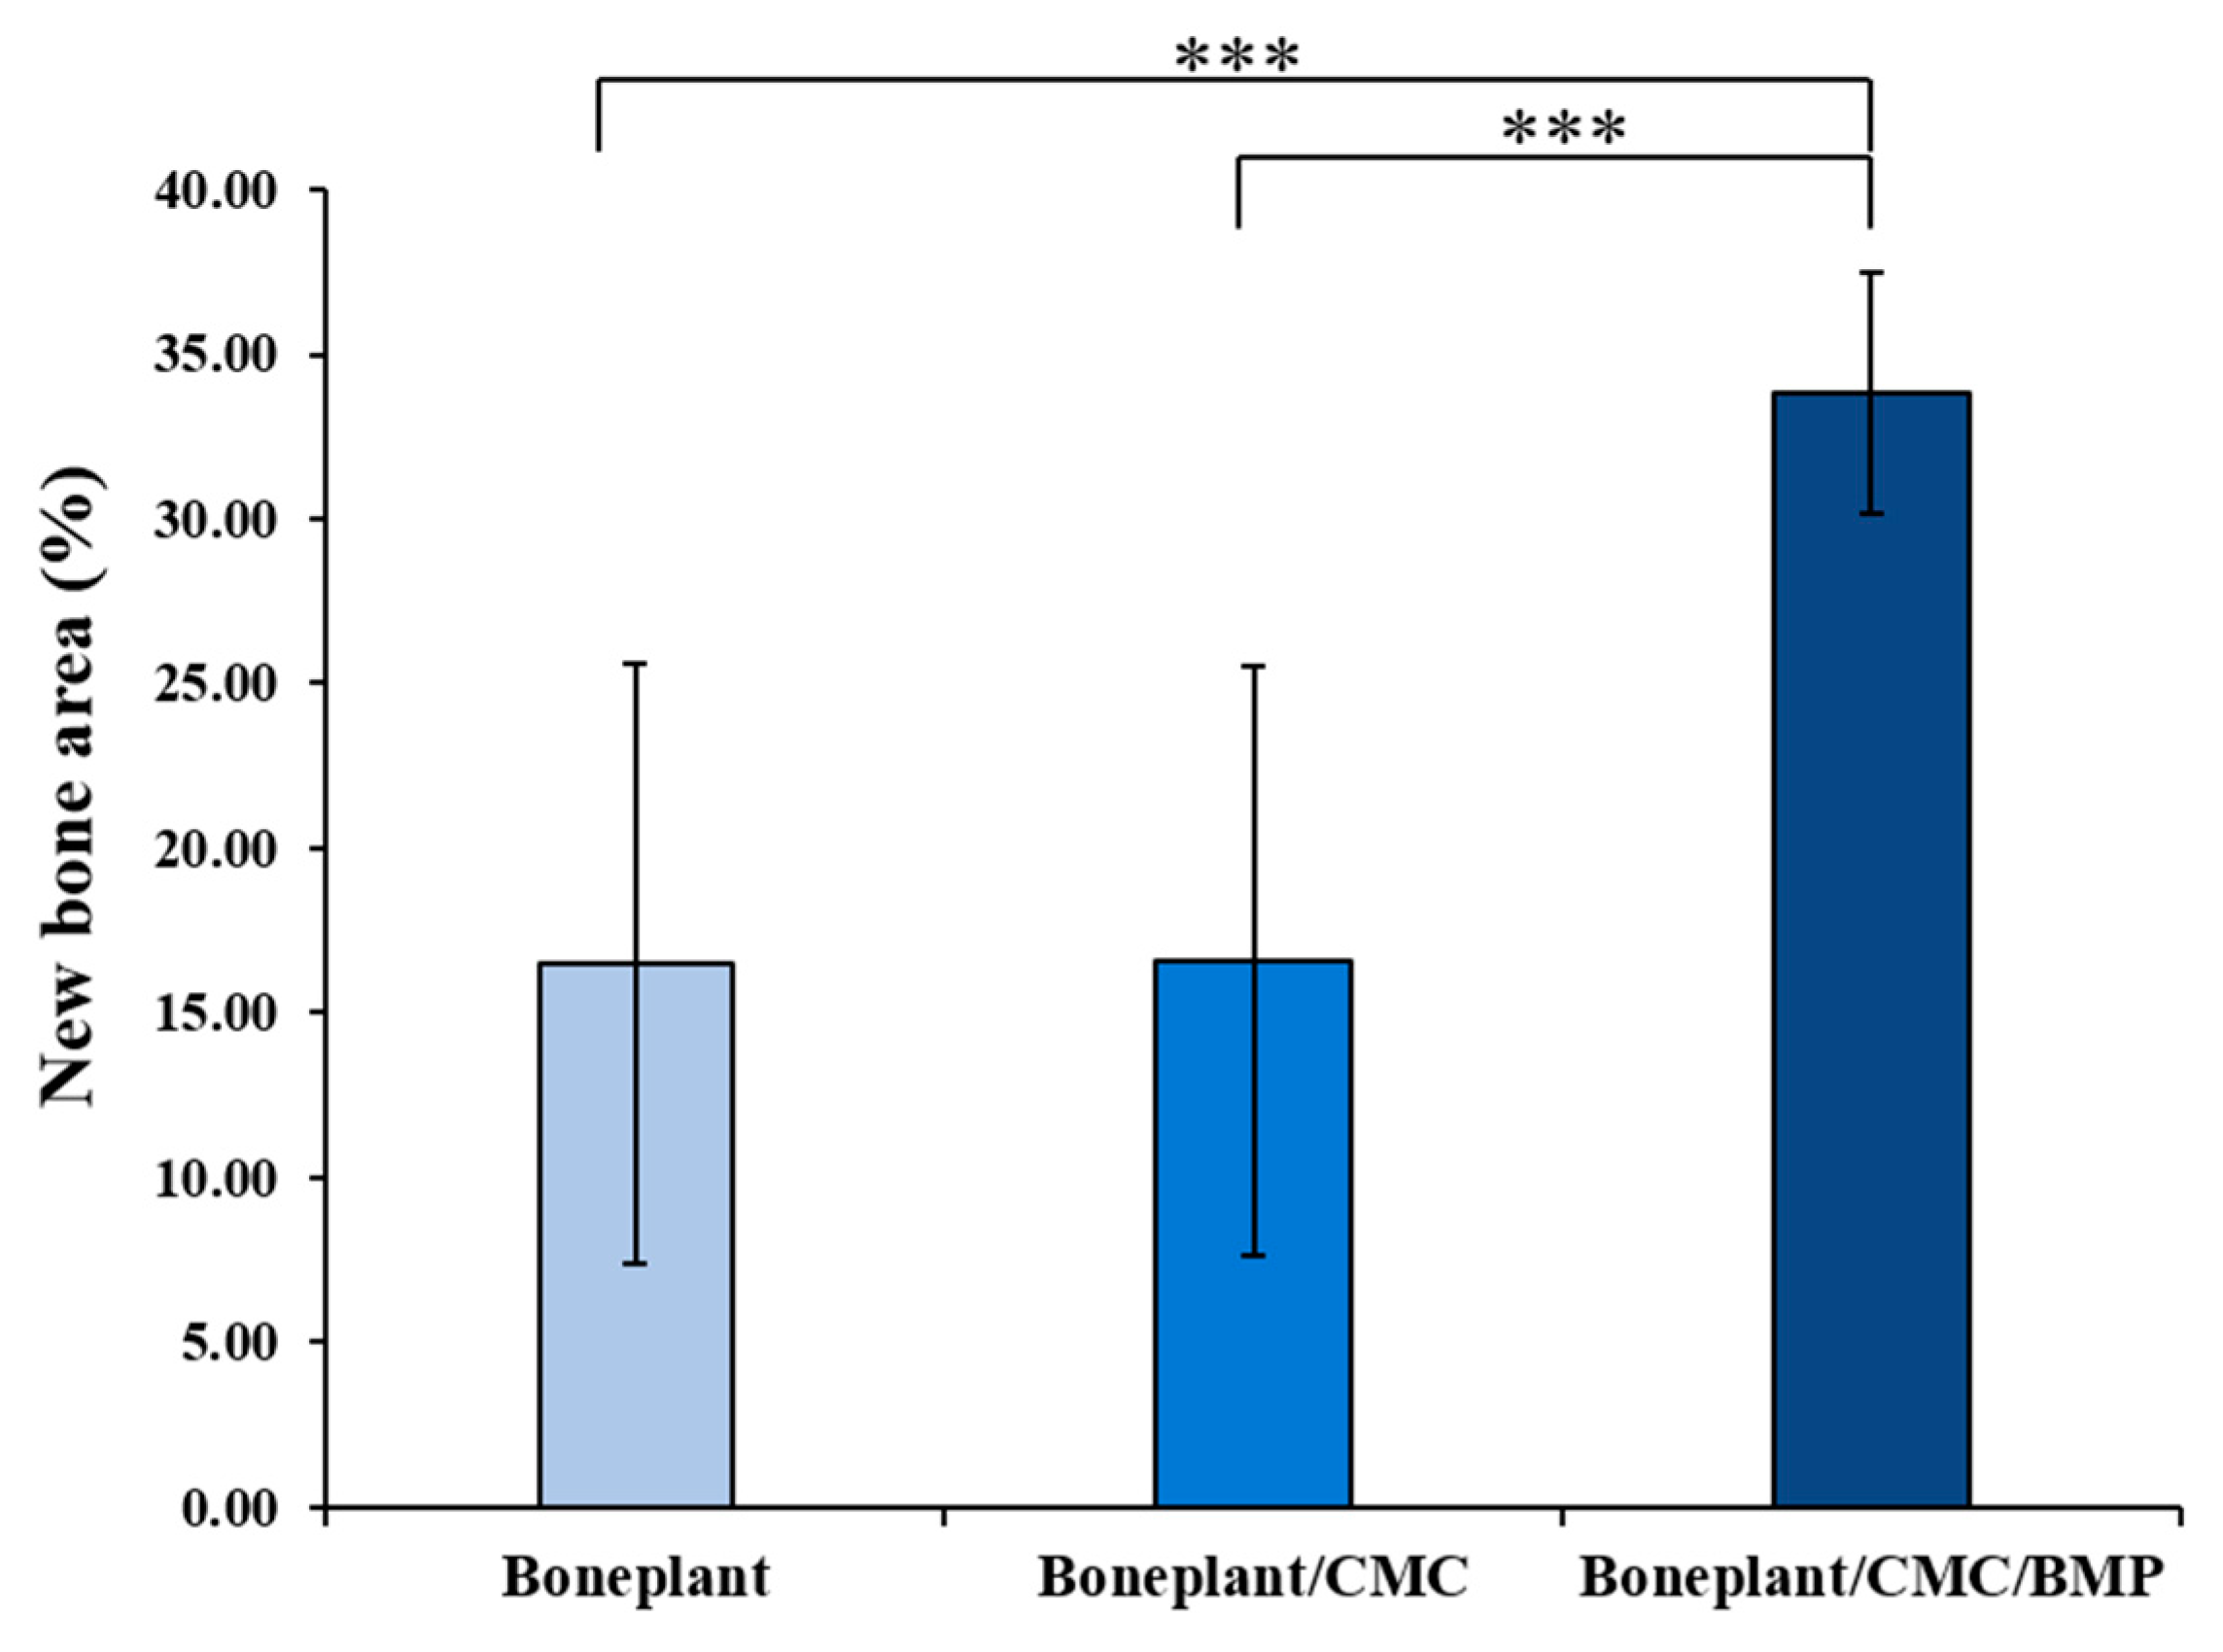

3.2.4. Histometric Findings

| Groups | Mean | SD | P-Value | |

|---|---|---|---|---|

| New Bone Area (%) | Boneplant | 16.48 | 9.11 | 0.000 *** |

| Boneplant/CMC | 16.57 | 8.94 | ||

| Boneplant/CMC/BMP | 33.79 | 3.66 |